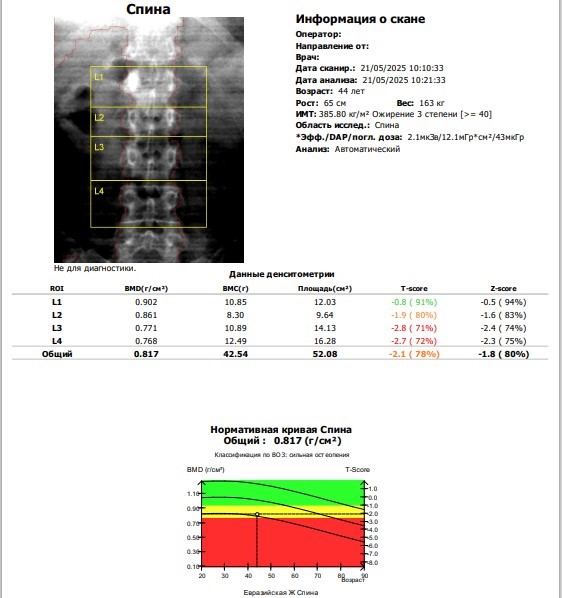

Результаты рентгеновской денситометрии (T-оценка)

Плотность костной ткани часто оценивается с помощью T-критерия или Z-критерия. T-критерий показывает, насколько плотность костной ткани пациента отличается от плотности костной ткани молодого человека того же пола в период максимальной плотности костной ткани.

- T-оценка ≥ -1 — нормальная плотность костной ткани.

- T-оценка от -1 до -2,5 — остеопения, указывающая на снижение плотности костной ткани, но не на остеопороз.

- T-оценка ≤ -2,5 — остеопороз, означающий значительное снижение плотности костной ткани и повышенный риск переломов.